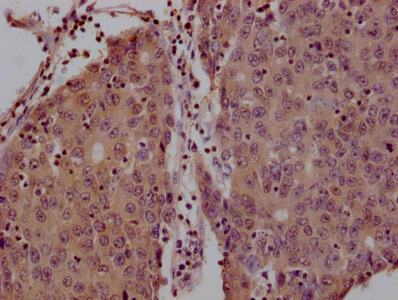

IHC image of CSB-MA026293A0m diluted at 1:200 and staining in paraffin-embedded human lung cancer tissue performed on a Leica BondTM system. After dewaxing and hydration, antigen retrieval was mediated by high pressure in a citrate buffer (pH 6.0). Section was blocked with 10% normal goat serum 30min at 37°C. Then primary antibody (1% BSA) was incubated at 4°C overnight. The primary is detected by a Goat anti-rabbit IgG labeled by HRP and visualized using 0.05% DAB.